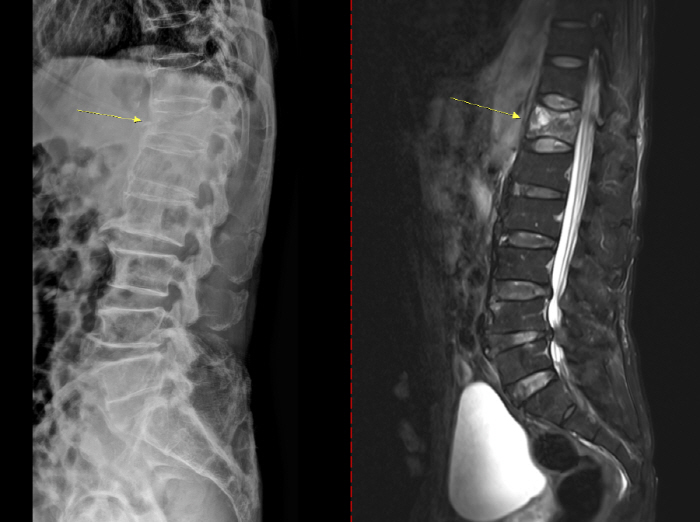

골다공증은 초기 징후가 뚜렷하지 않아 특히 주의해야 한다. 통증이나 자각 증상이 거의 없다가 시간이 지나 가벼운 충격만으로도 손목이나 대퇴골(엉덩이뼈)이 골절되면서 뒤늦게 진단되는 경우도 있다. 때로는 등이 굽거나 키가 줄어드는 척추 압박골절이 나타날 수도 있다. 치료 없이 방치하면 뼈는 점점 약해지고 척추와 손목, 대퇴골 골절 등 중대한 골절이 발생할 수 있다. 특히 대퇴골 골절은 고령 환자에서 수술 후 합병증, 장기 입원, 사망률 증가와 직결되는 중증질환이다. 척추 압박골절의 경우 자세 변화, 만성 통증, 보행 장애를 유발해 ▲활동량 감소 ▲근력 저하 ▲추가 골절의 악순환으로 이어진다.